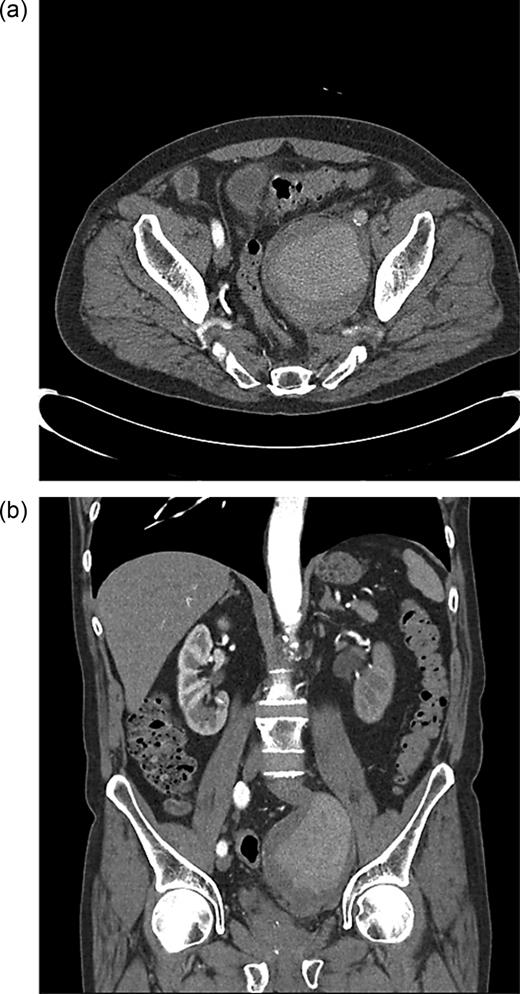

Orthopaedic review detected sensory loss in the S1 dermatome and foot drop on the left side. He was clinically well. Urgent magnetic resonance imaging (MRI) demonstrated a 9 cm left iliac aneurysm in contact with the left L5 nerve root and in close proximity to the S1 nerve root (Figure 1a and b). There was also left ureteric dilatation with hydronephrosis. The spinal cord was normal.

(a) T1-weighted sagittal MRI showing internal iliac aneurysm. (b) T1-weighted coronal MRI showing internal iliac aneurysm.

Computed tomography (CT) angiography was requested, and the patient was started on antibiotics because of the concerns over a mycotic aneurysm after discussion with the vascular team. CT angiography showed the internal iliac aneurysm obstructing the left ureter and abutting local nerve roots, with atheromatous disease within the common femoral arteries with an ectatic aorta (Figure 2a and b).